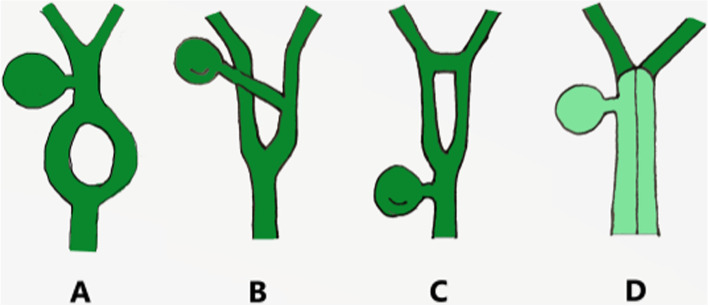

Duplication of the common bile duct is an extremely rare condition. The presence of double bile ducts is a normal step in human early embryogenesis. The definite lumen of the bile tree is developed by epithelial proliferation and vacuolization. As the vacuoles coalesce, they will initially create two parallel channels, which will gradually recede to form an isolated common anatomical structure of the common bile duct [ref. 4]. Regression failure of the double biliary system is considered to be the mechanism of type I anomaly [ref. 5].Chance elongation and early subdivision of the primitive hepatic furrow may be responsible for the other types of DCBD [ref. 6].The latest classification system of the DCBD proposed by Choi et al. [ref. 7] (2007) based on morphology which did not take into account of the aberrant CBD exits. They described five subtypes involving seven variants (Fig. 3). Since then, three new variants of double common bile duct were reported consecutively, however, none of these were classified into classification system [ref. 8–ref. 11] (Fig. 4). Our case is a new variant of diaphragmatic common bile duct duplication type I.The reason that why our case was classified as type I was that it was confirmed intraoperatively that there was a septum in common bile duct rather than two separate common bile ducts. The septum of original type I was located in the common bile duct. In our case, the septum in the common bile duct extended to the junction of the left and right hepatic ducts. The above-mentioned variants need a comprehensive classification to encompass these newly discovered variants. Thus, our classification system is as follows (Fig. 5): Type I, Partially (a) or completely (b) septum within the lumen; Type II, the distal bile duct bifurcates to two independent drainages; Type III, double biliary drainage without any communication (a), with intrahepatic communication (b); Type IV, double biliary drainage with extrahepatic communicating channels; TypeV, duplicated commen bile ducts join as a single biliary drainage channel,the gallbladder is attached to the repeated biliary ducts or Left or right hepatic duct (a), the gallbladder is connected to the common bile duct before or after separation(b). Our classification is including all types of common bile duct duplication reported in the present literature. Because of the location of the gallbladder junction and the location of the traffic between the repeated biliary ducts, our classification may contain additional variations not found.